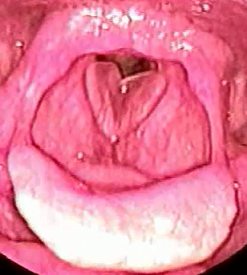

扁桃の病気

急性扁桃炎とは

風邪のウイルスへの感染や疲れ(疲労)が原因で喉にある扁桃が炎症を起こす病気です。

風邪のウイルスへの感染や疲れ(疲労)が原因で喉にある扁桃が炎症を起こす病気です。

症状は、発赤、膨張、発熱、疼通(喉の痛み)、嚥下時痛(飲み込むときの痛み)、全身倦怠感(体のだるさ・悪寒)、痛くて食事が食べられない等があります。

治療には副作用の少ない抗生物質の内服や点滴治療を行います。

年に数回、扁桃炎を繰り返し手しまう場合、手術を検討する必要があり、扁桃摘出術・扁桃切除手術の2種類の手術があります。入院が必要となりますので提携病院をご紹介いたします。

扁桃肥大とは

喉の奥にある扁桃(口蓋扁桃)が何らかの原因で肥大してしまう病気で、呼吸がしにくく、いびきや無呼吸症候群の原因にもなります。また、食事を飲み込むのに時間がかかります。治療には手術が必要な場合もあります。

喉の奥にある扁桃(口蓋扁桃)が何らかの原因で肥大してしまう病気で、呼吸がしにくく、いびきや無呼吸症候群の原因にもなります。また、食事を飲み込むのに時間がかかります。治療には手術が必要な場合もあります。